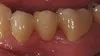

Fixed Bridges

Before: 3 Unit bridge with chipped porcelain molar (supporting metal showing on molar tooth), poor enamel color match to patient's natural teeth, and poor fit around the patient's gumline. After: Replaced Bridge with an All Porcelain Bridge. The new bridge now also matches the patient's natural tooth color and was designed to properly fit around the gumline. Proper fit aids in decreasing decay and the ease of the patient's ability to clean around a bridge.